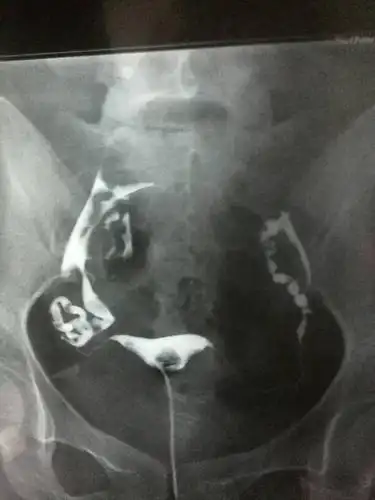

问:昨天做了输卵管造影,检查诊断是,右侧输卵管积水,两侧输卵管上举